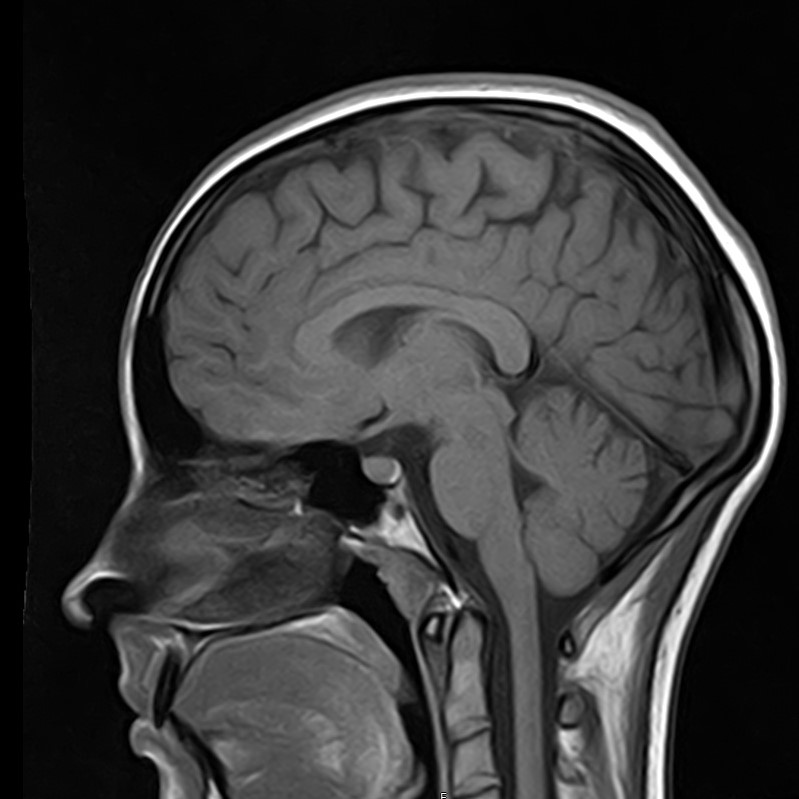

3. При головной боли, надо обязательно сделать МРТ

Действительно, зачастую приходят на МРТ пациенты, страдающие головной болью. Однако, в подавляющих случаях, МРТ не дает каких-то неблагоприятных результатов. Такая головная боль, как правило, связана с психоэмоциональными или психофизиологическими особенностями как организма, так и образа жизни (стресс, переутомление, несоблюдение режима труда и отдыха и т.д.). Но стоит отметить, что проведение МРТ даст дополнительную информацию Вам о состояние головного мозга и тем самым “успокоит” Вас.